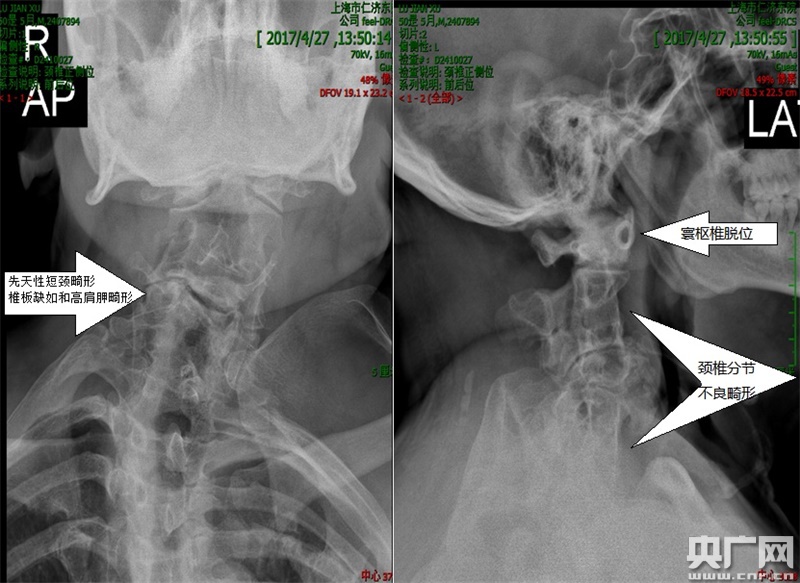

術(shù)前頸椎正側(cè)位X片,正位可見(jiàn)先天性短頸畸形、椎板缺如和高肩胛畸形,側(cè)位可見(jiàn)寰樞椎脫位、頸椎分節(jié)不良畸形。